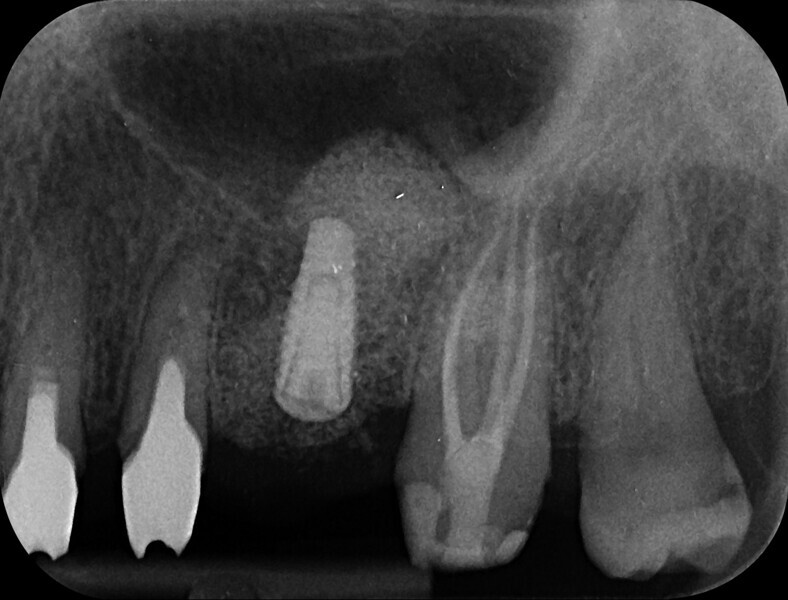

Minimally invasive root canal shaping—A new protocol